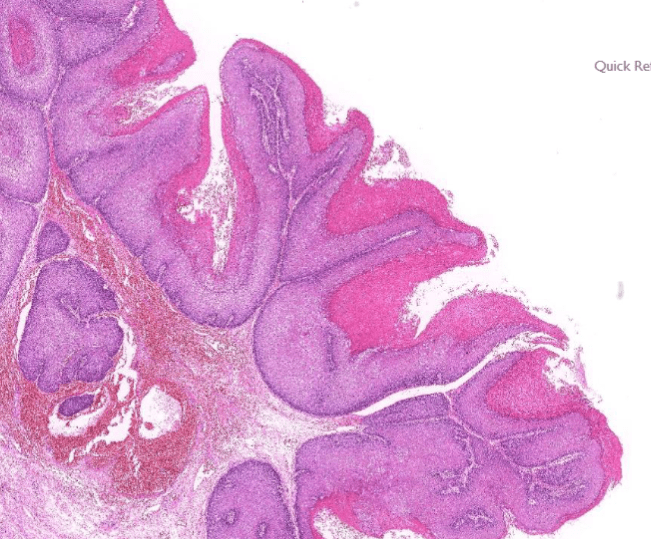

2. epithelial infoldings and papilla